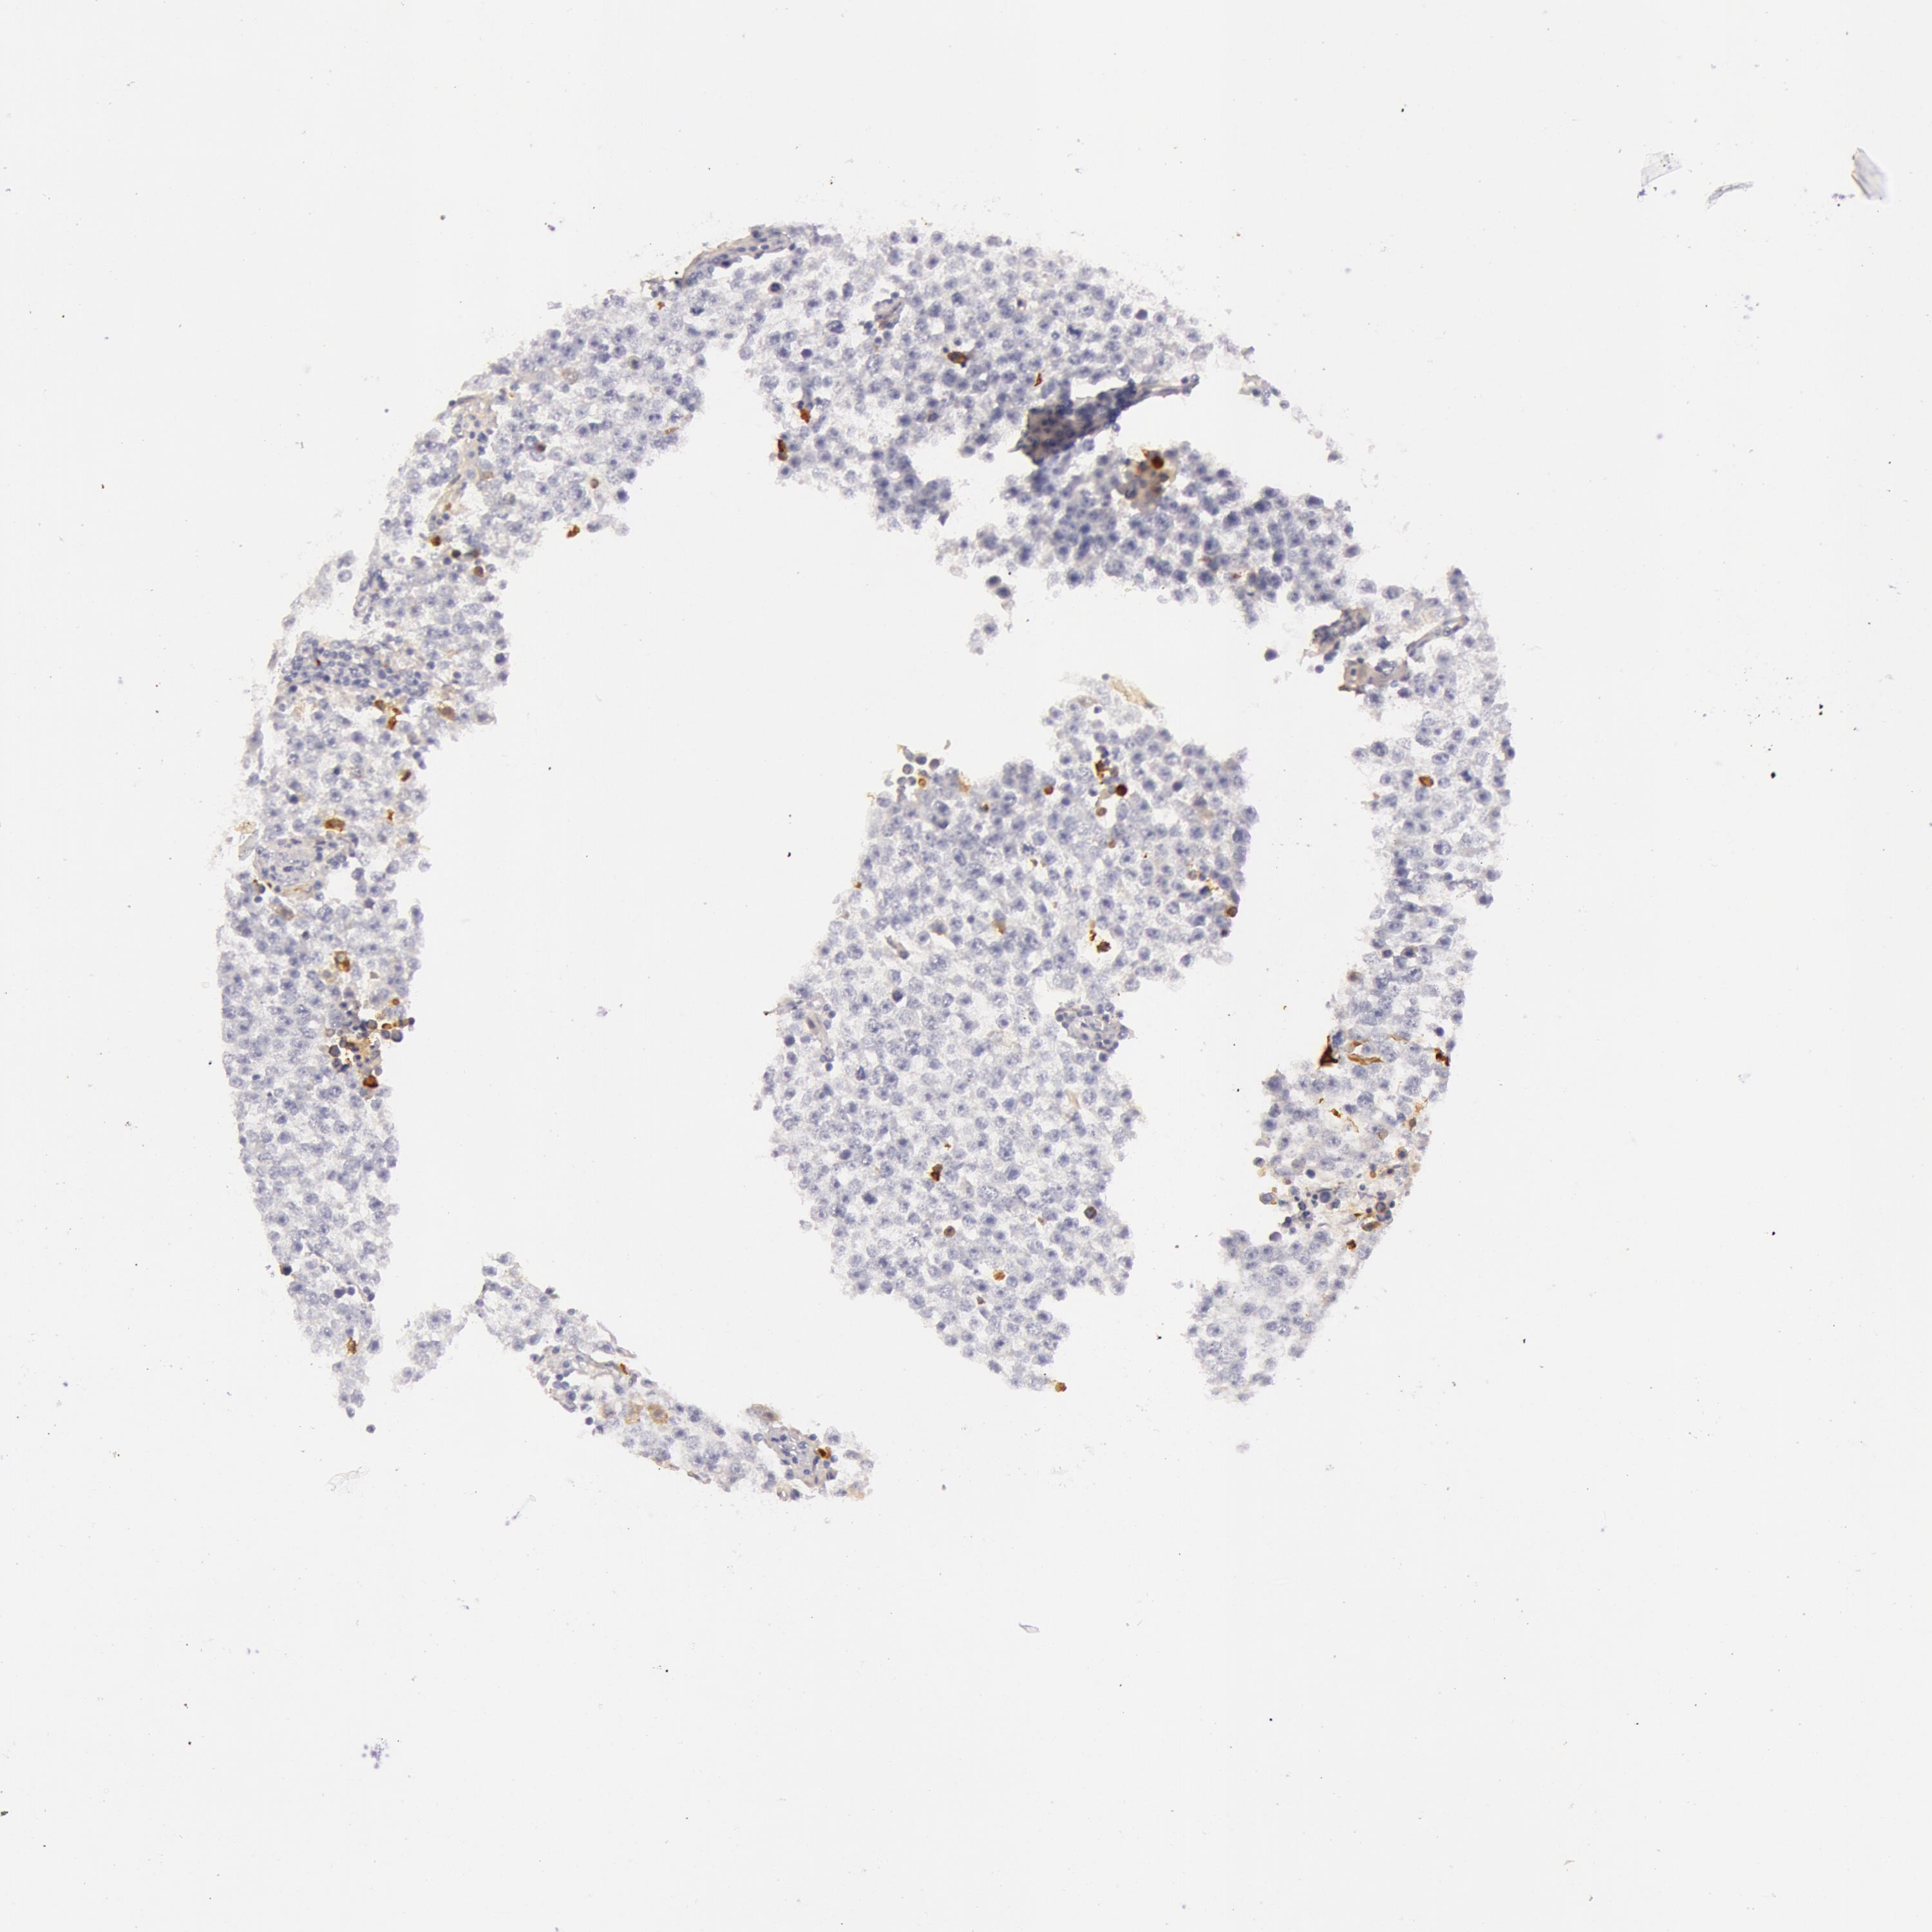

TESTIS CANCER - Protein expressioni

A mouse-over function shows sample information and annotation data. Click on an image to view it in a full screen mode. Samples can be filtered based on level of antibody staining by selecting one or several of the following categories: high, medium, low and not detected. The assay and annotation is described here.

Note that samples used for immunohistochemistry by the Human Protein Atlas do not correspond to samples in the TCGA dataset.

Antibody stainingi

Antibody staining in the annotated cell types in the current human tissue is reported as not detected, low, medium, or high, based on conventional immunohistochemistry profiling in selected tissues. This score is based on the combination of the staining intensity and fraction of stained cells.

Each image is clickable and will lead to virtual microscopy that enables deeper exploration of all samples and also displays staining intensity scores, fraction scores and subcellular localization as well as patient and tissue information for each sample.

Antibody HPA000926

Seminoma, NOS

Carcinoma, Embryonal, NOS